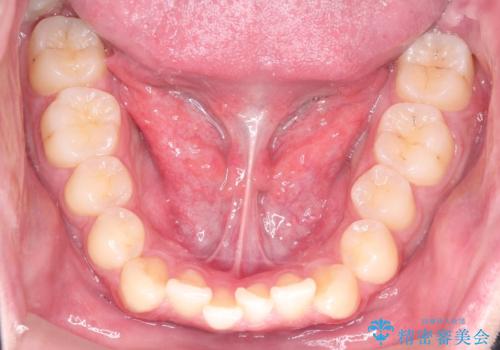

初診時の歯並びの状態としては、上下ともに前歯部の中等度以上のがたつき(叢生)があり、右の前歯が1本飛び出した状態でした。

抜歯は行わず上下顎ともに、主に歯列弓の拡大とディスキング(歯と歯の間に隙間を作る処置)を行い叢生を改善しました。